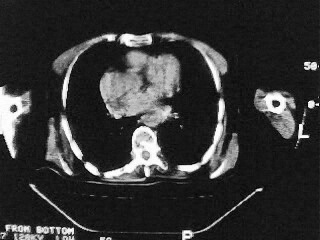

女,79,咳 嗽月余,无其它不适

1)两肺炎症。2)食管裂孔疝可能;建议行上消化道钡餐检查。

后纵隔内左心房至肝左叶后方椎体中线偏左巨大软组织包块,其壁均匀比较薄,其内可见宽气液平。

考虑食管裂孔疝。建议钡餐检查